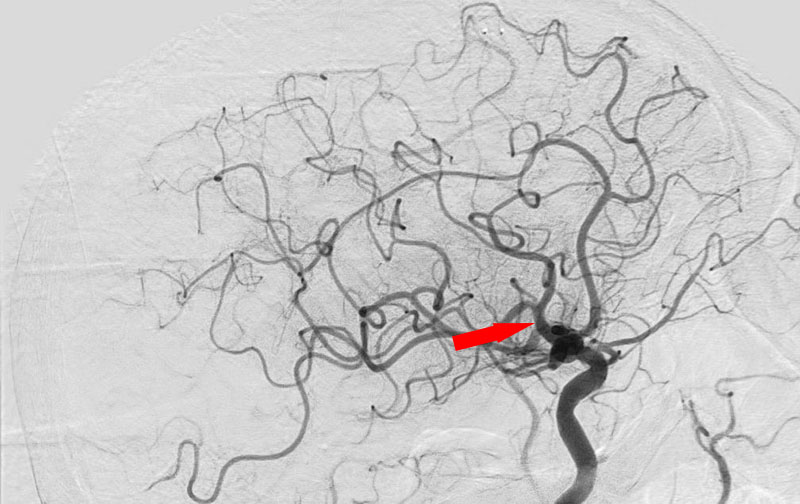

No.1091 手術中

脳動静脈奇形

20代

大阪府の病院